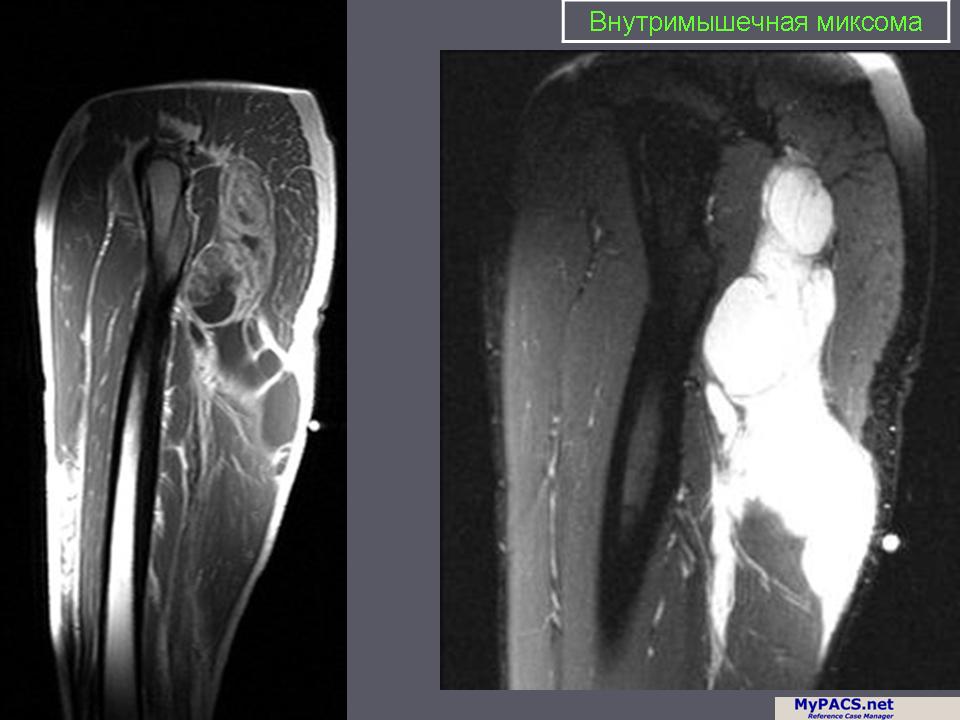

Внутримышечная миксома

Внутримышечная миксома — довольно редкая опухоль, поражающая бедро, ягодичную мышцу, реже другие места у 59—70-летних лиц, обычно женщин. Макроскопически представляет собой округлое, четко отграниченное образование диаметром 4—10 см, студенистой консистенции, в котором могут обнаруживаться мелкие кисты и фиброзные трабекулы. У 5 % больных, как правило, страдающих сочетанным полиостозом, внутримышечная миксома бывает множественной. Под микроскопом границы миксомы неотчетливы, создается иллюзия инвазии в окружающие мышцы и фасции. Рассеянные и крайне малочисленные мелкие клетки разной формы, а также пузыревидные муцифаги лежат в обильно представленном муцине, богатом кислыми мукополисахаридами. Опухоль нужно дифференцировать от миксоидной злокачественной фиброзной гистиоцитомы, миксоидной нейрофибромы и миксоидной липосаркомы